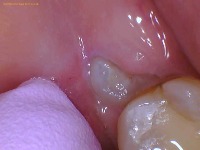

These are two pictures of a real lower wisdom tooth coming in through the gums. The first and second photo were taken a couple of months apart but they are of the same patient.

These are two pictures of a real upper wisdom tooth coming in through the gums. The two photos were taken a couple of months apart on the same individual.